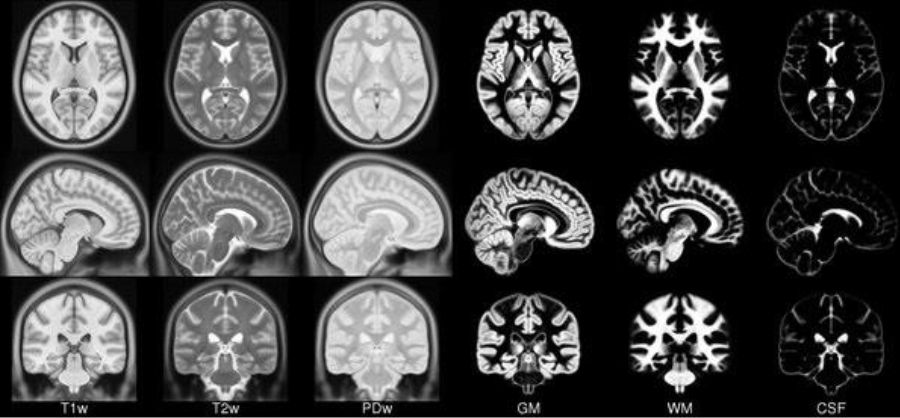

Before introducing the dataset it is important to point out that there exist two types of MRI: T1-weighted and T2-weighted images. In MRIs, the magnetically sensitive hydrogen nuclei align with the fields created by the MRI. The radio waves released by the scanner are then absorbed as energy by the nuclei. When the radio waves stop, the nuclei return to their initial state, emitting tiny energy signals that the computer uses to create visual images. This signal has two components:

Initially, the longitudinal signal is weak because most nuclei are tilted to the axis. However, this signal grows as the nuclei realign. The time constant that determines the realignment speed is denoted T1. Conversely, the transverse signal is strong because most nuclei are in phase coherence. The signal decays as the nuclei go out of phase as they realign. This decay is indicated by the time constant T2[9]. The differences in T1 and T2 relaxation times control the contrast of the MRI and depending on the case their values are modelled to have more or less contrasted images.

We focus on a single type of MRI and we selected T2-weighted images because the contrast and brightness are predominantly determined by the T2 properties of tissue [28].

Figure 6: Example of templates.